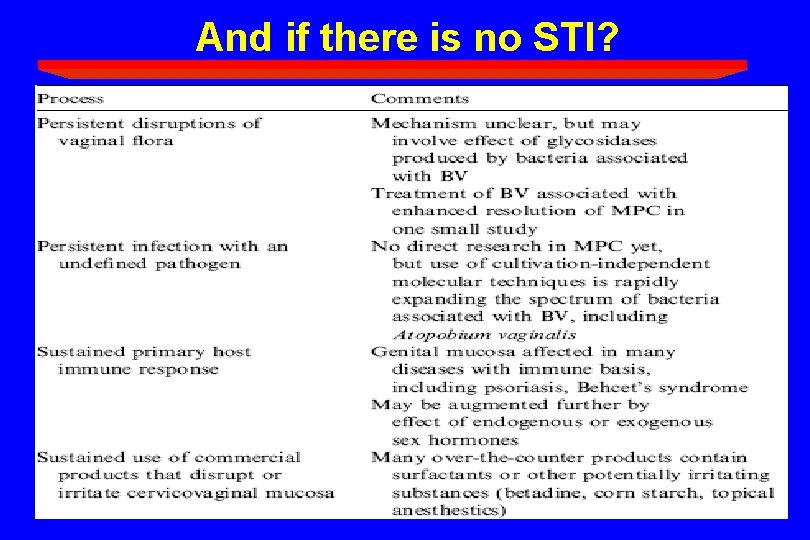

And if there is no STI?